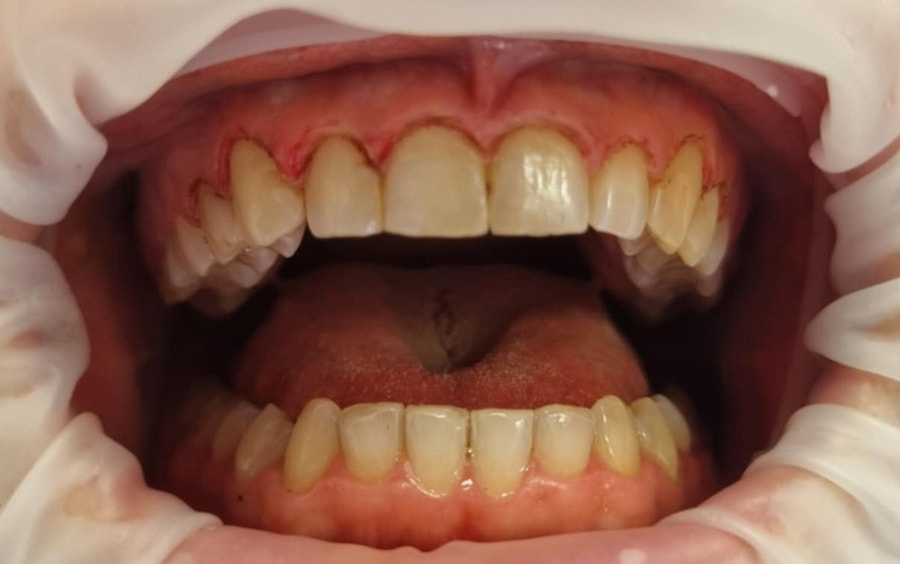

Przykład zabiegu gingiwektomi

Po

Zabieg gingiwektomi po